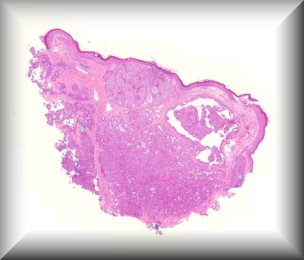

Hind M. Alkatan (Guest): A 10-month-old boy presented with a painless scrotal mass.External examination demonstrated left scrotal non-tender hard mass measuring 4x3 cm in size, with negative transillumination test. Ultrasonography of left scrotum showed a well-circumscribed, oval shaped mass with mixed echogenicity, The mass contained both cystic and solid component, with no clear visualization of the left testicle.The patient underwent left scrotal exploration with high inguinal orchidectomy |